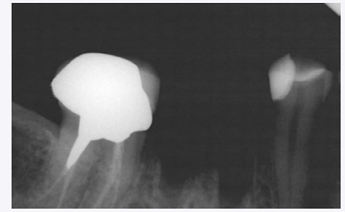

Periapical radiograph after tooth extraction.

A 39-year-old woman presented with a failing mandibular right first molar under a fixed PFM prosthesis. The patient was in good health and had no medical contra-indications that would prevent routine dento-alveolar surgery. Pre-operative photographs and periapical radiographs were taken of the site. After bridge removal, the tooth was deemed hopeless. It was sectioned and extracted in an atraumatic manner using periotomes and luxators (Figs. 1-3).